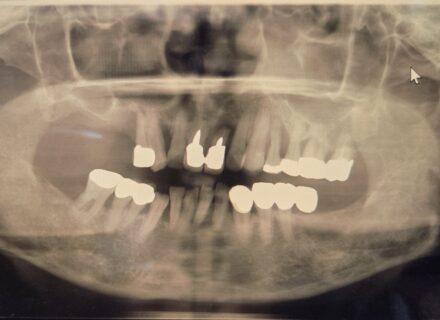

8年経過したインプラント症例:前歯の違和感を訴える40代女性患者 はじめに インプラント治療後の長期経過観察は、治療の成功を評価する上で非常に重要です。今回、8年前にインプラント治療を行った40代…